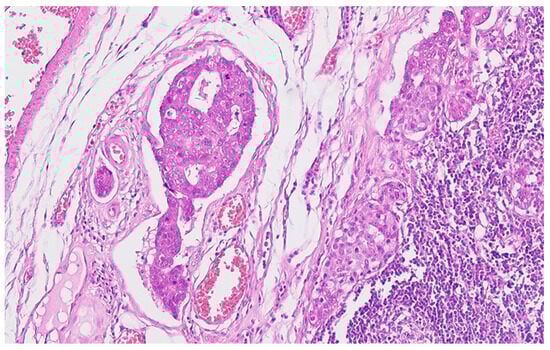

Collision Tumors of the Colon and Peritoneum: Signet-Ring Cell Carcinoma and Granular Cell Tumor

2. Case Report

Histopathological Findings